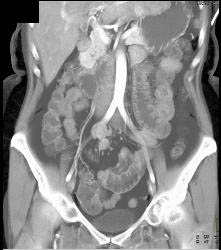

Subtle Multiple Carcinoid Tumors in Small Bowel Show Best on 3D MIP